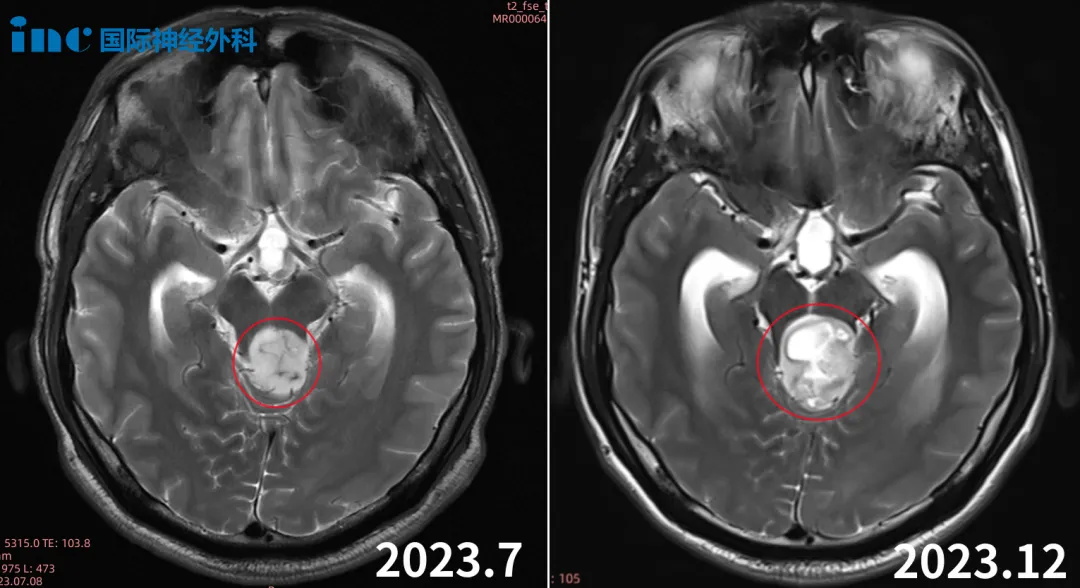

36岁男性-脑干胶质瘤并发梗阻性脑积水

36岁的贺先生,2022年7月由于晨起出现头晕、头痛、恶心呕吐等症状就医检查,CT、核磁检查提示:中脑顶盖区域肿瘤性病变,大小约18*21*20mm,增强扫描呈环形强化、壁薄。

中脑顶盖肿瘤,这个消息对一家人来说无疑是个晴天霹雳。问诊过10位神经外科专家,有建议手术的、有建议观察并半年后复查的,还有说这个区域不建议手术的,没有医生建议放化疗或不同治疗。

然而,肿瘤却一直在长大,症状也再一步步加重……

多方查询下,他们找到INC旗下国际神经外科顾问团成员——国际脑干手术教授巴特朗菲教授。为了能够尽快顺利手术,他们决定咨询巴教授。

巴教授回复:手术需完全切除肿瘤,这是首要目的。因此,一步是治疗脑积水,二步是完全切除肿瘤,三步根据结果,我们可以做出决定(关于术后的辅助治疗)。

得到巴教授的肯定回复后,他们决定争取巴教授2024年1月示范手术机会。

2024年1月10日,巴教授率领国内团队共同的努力下,手术取得了成功。